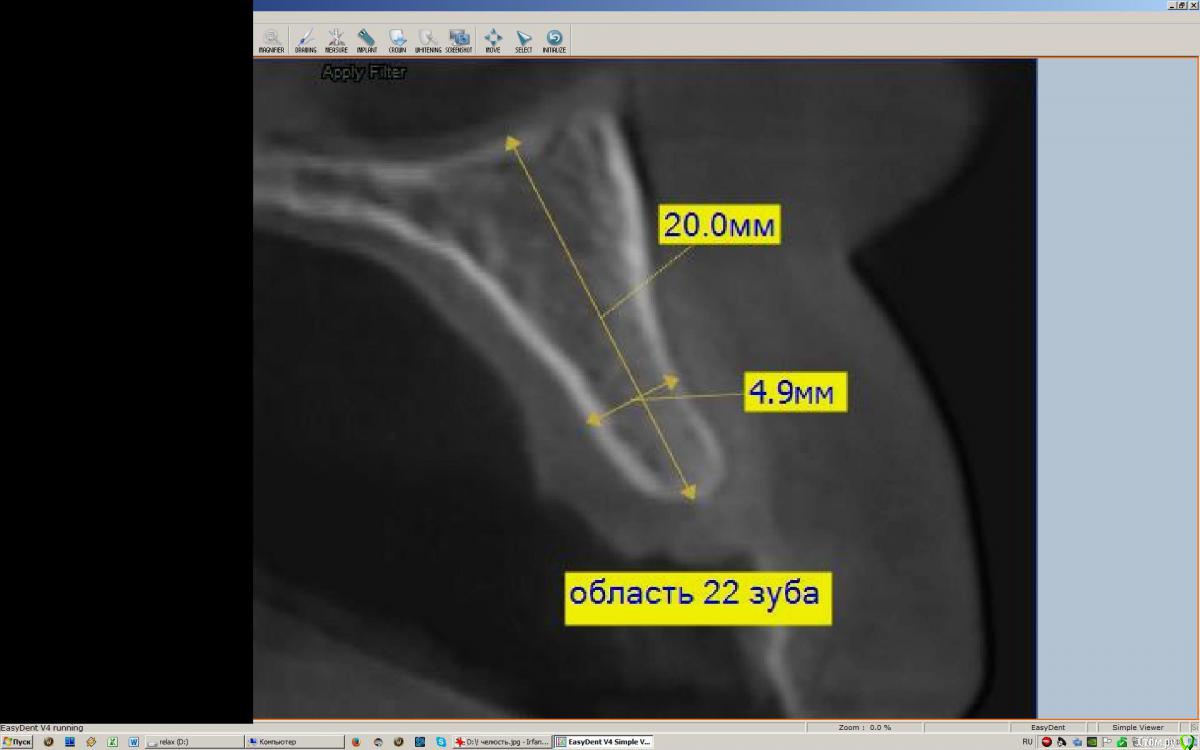

dsfksdkf Опубликовано 14 ноября, 2015 Автор Поделиться Опубликовано 14 ноября, 2015 Снимок не совсем информативен, не понятно на какой высоте эти срезы. Но в подобной ситуации, я бы поставил импланти делал НКР или расщепление с НКР, но не костный блок. P. S. Личные данные со снимков лучше убирать.Скажите пожалуйста что такое НКР? может вот этот снимок подойдет Ссылка на комментарий

red_butler Опубликовано 14 ноября, 2015 Поделиться Опубликовано 14 ноября, 2015 Скажите пожалуйста что такое НКР? может вот этот снимок подойдетНаправленная костная регенерация.Да с этим снимком все встало на свои места.Технику костной пластики выбирает врач, Вы выбираете врача. 1 Ссылка на комментарий

dsfksdkf Опубликовано 14 ноября, 2015 Автор Поделиться Опубликовано 14 ноября, 2015 Направленная костная регенерация. Да с этим снимком все встало на свои места. Технику костной пластики выбирает врач, Вы выбираете врача. а Вы что рекомендуете в связи с последним снимком? Ссылка на комментарий

red_butler Опубликовано 14 ноября, 2015 Поделиться Опубликовано 14 ноября, 2015 а Вы что рекомендуете в связи с последним снимком? Но в подобной ситуации, я бы поставил имплант и делал НКР или расщепление с НКРи работа с мягкими тканями Ссылка на комментарий

dsfksdkf Опубликовано 14 ноября, 2015 Автор Поделиться Опубликовано 14 ноября, 2015 (изменено) в принципе, меня мало эстетика волнует , главное функциональность и чтобы проблем не было. И очень -очень интересует вопрос поместится ли туда тонкий имплант , если не наращивать кость и ничего не делать, и при этом чтобы он полностью со всех сторон был бы погружен в кость, то есть, чтобы имплант не контактировал с мягкими тканями? Изменено 14 ноября, 2015 пользователем dsfksdkf Ссылка на комментарий

dsfksdkf Опубликовано 1 декабря, 2015 Автор Поделиться Опубликовано 1 декабря, 2015 (изменено) У меня последний вопрос, чтобы выбрать врача и выбор был правильным мне необходимо знать это... Скажите пожалуйста в моем случае возможно ли без расщепления и вообще какой либо костной пластики, погрузить имплант 3, 5 в кость, которая имеется, нёбно? То есть не выводя имплант за пределы кости? И чем это чревато? Изменено 1 декабря, 2015 пользователем dsfksdkf Ссылка на комментарий

dsfksdkf Опубликовано 2 декабря, 2015 Автор Поделиться Опубликовано 2 декабря, 2015 (изменено) я скорее всего вообще бы не наращивал кость в данной ситуации.тоже не хочется наращивать, но 1 врач говорит что имплант должно окружать как минимум 1 мм, а лучше 2мм, что кость питалась и не рассасывалась, а у меня не хватает. То есть 3, 5 мм имплант и 4, 7 мм кость . Если это так ( так ли это?),то мне бы не хотелось потерять в будущем имплант или чтобы он оголился и пр. негативные последствия... Изменено 2 декабря, 2015 пользователем dsfksdkf Ссылка на комментарий